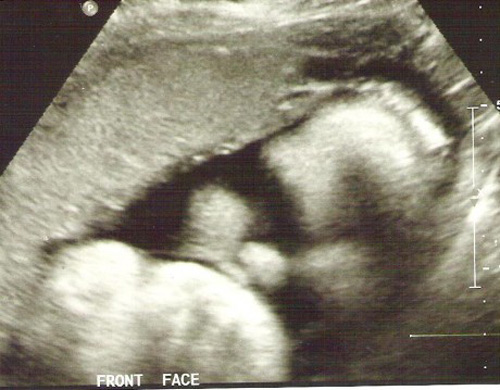

Một bà mẹ người Mỹ vô cùng vui mừng khi biết mình mang thai.Tuy nhiên đến tuần thứ 22 tiến hành siêu âm thai nhi,quá bất ngờ khi nhận được kết quả.Bà mẹ chia sẻ câu chuyện của mình khiến nhiều người cảm động.

Chúng tôi lại chờ đợi đến tuần 22 mới quyết định siêu âm để xem hình thái của con. Vậy nhưng sau 22 tuần chờ đợi, chúng tôi lại nhận về một tin như “sét đánh”.

Nữ y tá siêu âm cho tôi nói chúng tôi có một bé gái nhưng cô không thể nhìn thấy bàn chân bên trái của con bé đâu. Y tá nói cô phải đưa kết quả cho bác sĩ kiểm tra lại.

Tại lần siêu âm thứ 2 ở tuần 26 thai kỳ, bác sĩ đã khẳng định lại một thực tế là con gái tôi không có bàn chân trái nhưng vẫn có khớp gối. Ngoài ra, bàn tay con bé dường như nắm chặt và không thể mở ra. Ông giải thích thêm rằng có thế bé đã gặp dị tật do di truyền. Sức khỏe tại thời điểm đó của con rất tốt, chỉ là không có bàn chân bên trái và bàn tay không mở được.